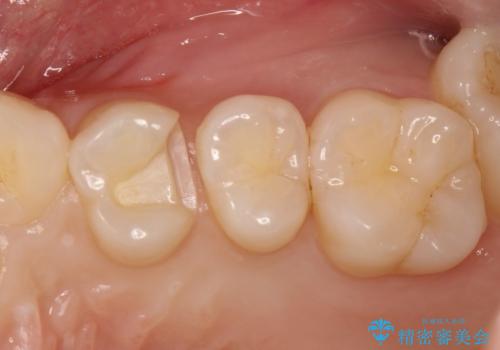

気づかないうちに大きな虫歯が 神経を保存し、セラミックで修復

- 神経を温存し、セラミックインレーによる修復をおこなった。

詰め物の種類:e.max press